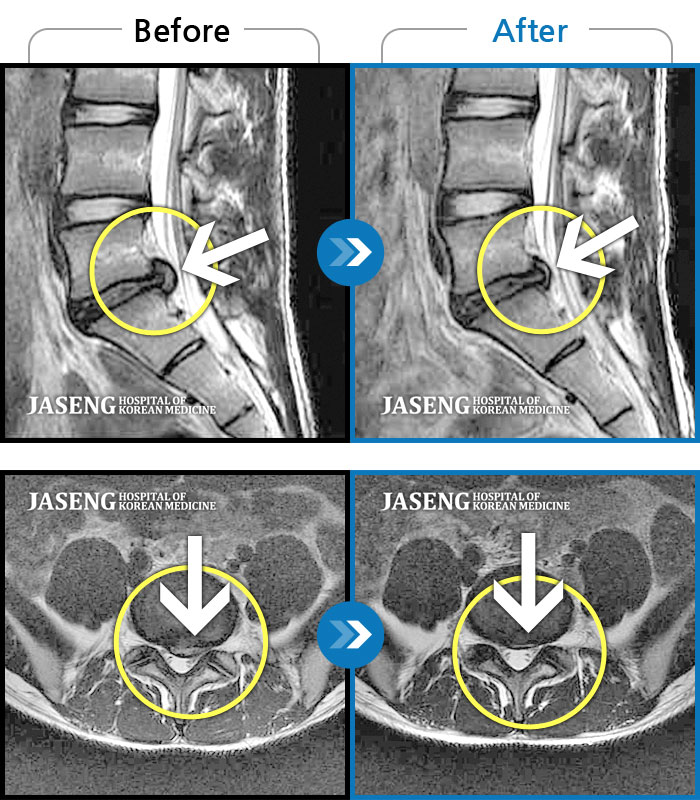

허리디스크

수원 · 김태성 원장

허리 통증과 우측 고관절~하지방사통이 심하여 활동하기 힘든 상태

촬영시기

2021.03.04 ~ 2021.10.06

2022.03.25